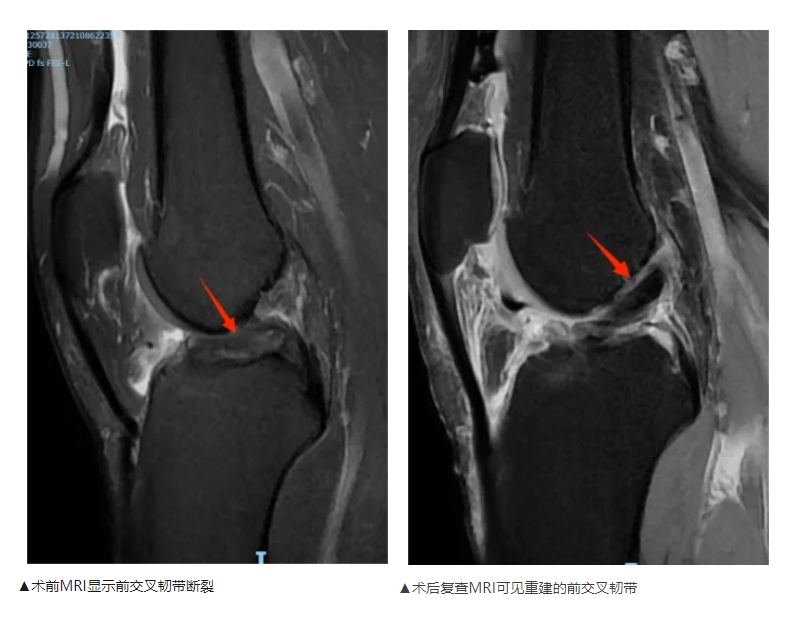

【治疗难度】:前交叉韧带完全断裂,传统重建术存在肌腱切割、骨隧道扩张及腱骨愈合慢等生物力学缺陷

【治疗效果】:术后复查显示,重建的韧带位置良好,固定牢固。